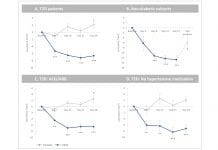

AMPK activator O304 – a novel treatment for Type 2 diabetes and diabetic kidney...

The high and increasing unmet patient need in diabetic kidney disease demands new drugs. Betagenon AB has the answer.

Globally, approximately 40% of Type 2...